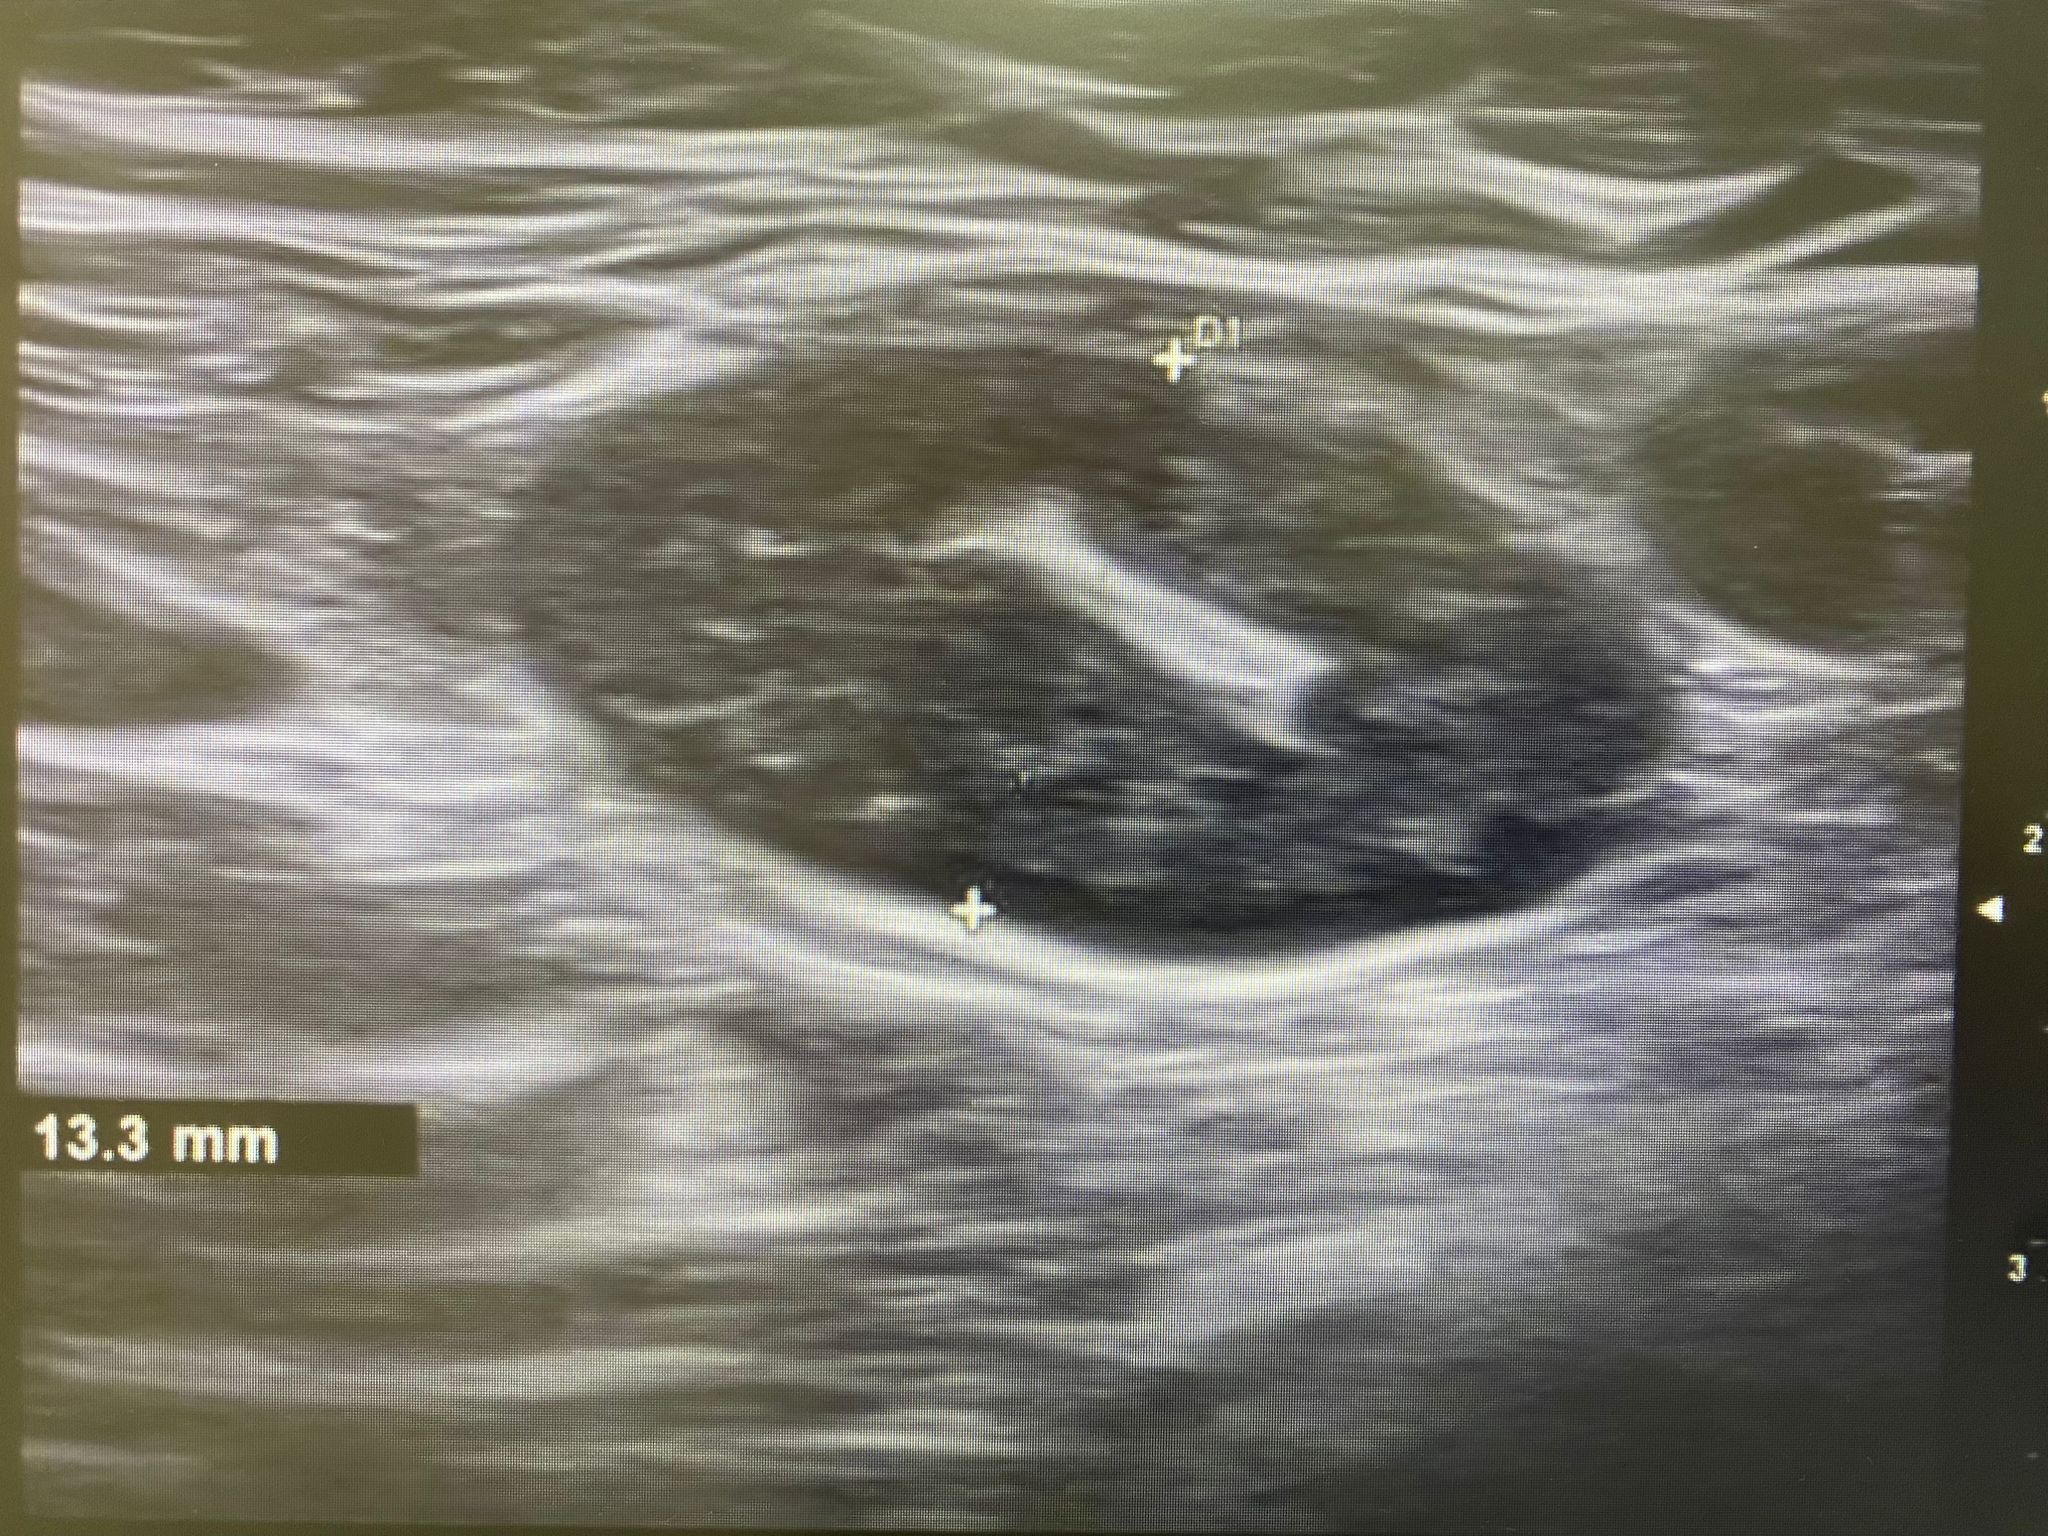

Ecografía: Valoración de adenopatías para acercamiento diagnóstico (típicas/atípicas).

Adenopatías patológicas, algunas redondeadas, con eje anteroposterior > 1 cm, parénquima homogéneo, cortical engrosada aunque con hilio respetado.

Ecografía mamas: quistes y nódulos hipoecogénicos bilaterales.

Ecografía axilar: múltiples adenopatías con eje corto > 2 cm y cortical engrosada.